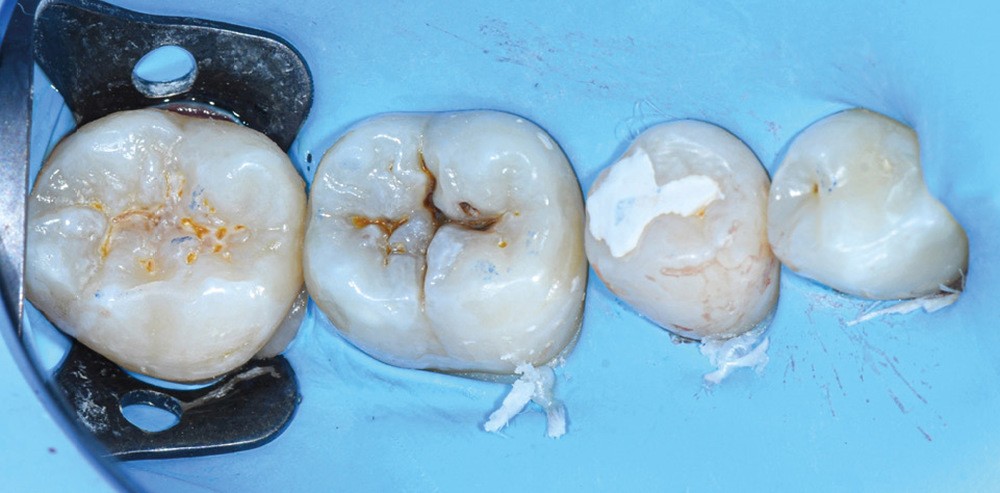

Nous détaillons la technique à travers le cas d’une jeune fille de 18 ans présentant des lésions carieuses sur quatre dents (fig. 1 à 14).

Cette technique de tampon occlusal est indiquée lorsque la face occlusale de la dent à reconstruire est fonctionnelle. Elle évite les multiples incréments occlusaux de résine composite. En contrepartie, elle demande un peu d’entraînement, notamment pour bien replacer le tampon et doser correctement la quantité de résine composite à appliquer avant de tamponner la face occlusale. Néanmoins, une fois maîtrisée, elle est rapide et offre une grande reproductibilité de la situation occlusale de départ en s’évitant les potentielles retouches fastidieuses de fin de séance.